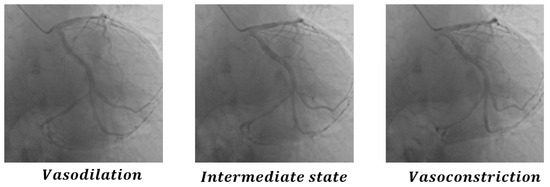

| Metric | Vasodilation & Intermediate | Vasodilation & Vasoconstriction | Intermediate & Vasoconstriction |

|---|---|---|---|

| CDKD-w+ | 0.998 | 0.996 | 0.998 |

| L1 LOSS | 26.11 | 22.39 | 29.10 |

| PSNR | 33.86 | 34.58 | 32.92 |

| SSIM | 0.862 | 0.878 | 0.846 |

| ResNet | 0.984 | 0.997 | 0.991 |